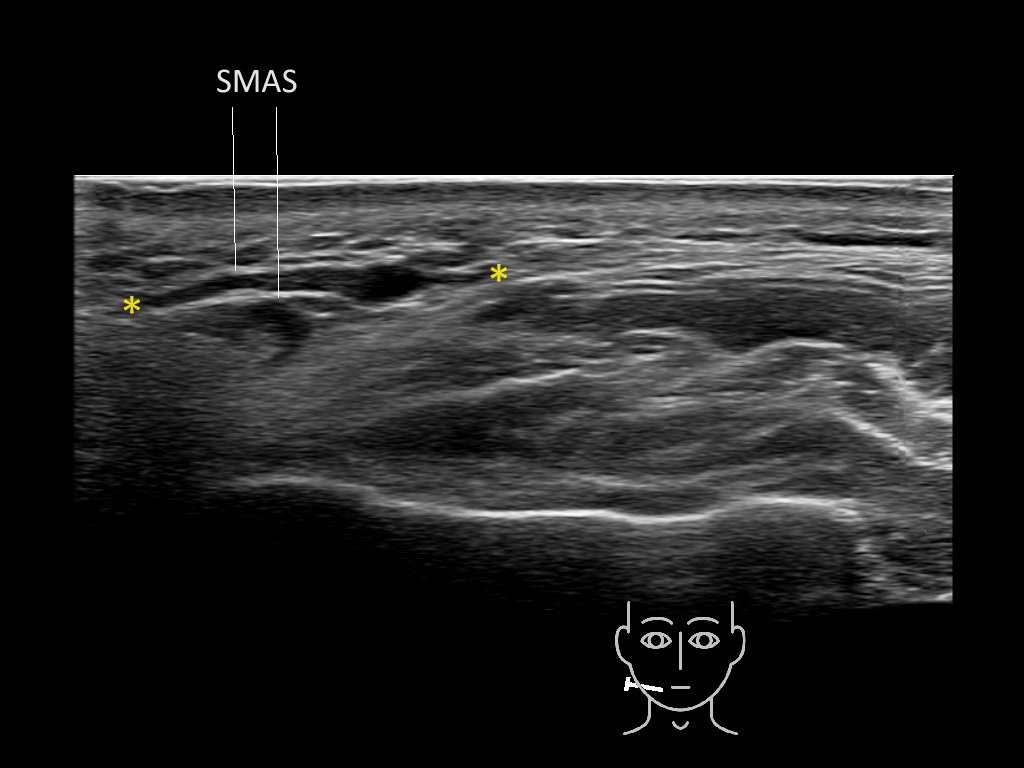

Filler deposits may end up unintentionally in the SMAS or fascial layers of the skin. Very often this will not lead to adverse events, however, adverse events ( nodules, migration / redistribution impaired muscle movement and smiling and malar edema) are are often related to filler ending up in the SMAS or fascia.

Study the first image to recognize the different layers. If you are sure about the layers, swipe to the second image to view the answer (if applicable).